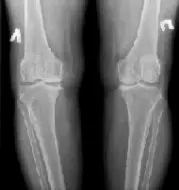

Картина, видима при рентгені коліна

Знімки робляться в двох проекціях: передньо-задній (прямий) і бічний. В першу чергу на рентгенограмі лікар-рентгенолог бачить анатомічна будова колінного суглоба

У процесі розшифровки рентгена колінного суглоба, лікар оцінює стан кісток, ширину суглобової щілини, наявність або відсутність остеофитов на бічних поверхнях стегнової і великогомілкової кісток, розташування і стан надколінка.

Рентген колінного суглоба в нормі і при різних патологіях

норма

На рентгені колінного суглоба в нормі не повинно визуализироваться ніяких патологічних новоутворень; тріщин, осколків. Суглобові поверхні – рівні, суглобова щілина однакова по ширині з обох сторін. Надколінок непошкоджений, що не зміщений.